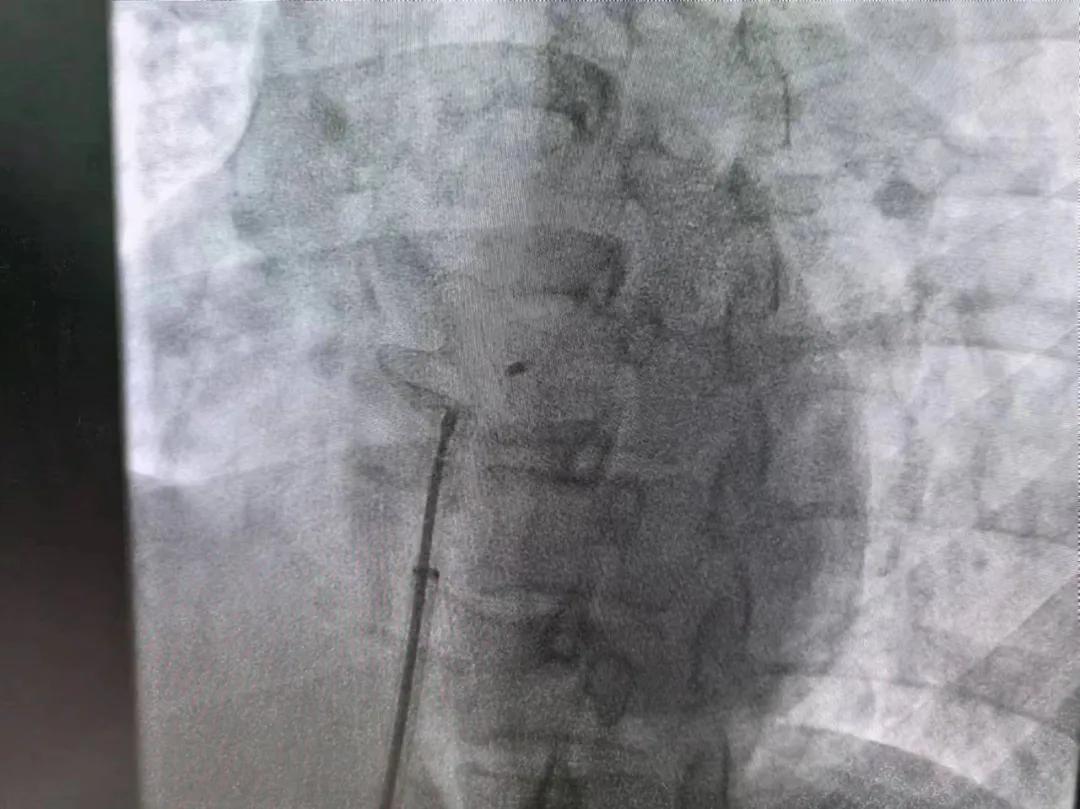

繼3月14日市二院成功開展首例卵圓孔未閉介入封堵術(shù)之后,3月21日上午,市二院院長(zhǎng)王瑾及心血管內(nèi)科主任李慧新帶領(lǐng)心血管內(nèi)科介入團(tuán)隊(duì),再次成功為患者實(shí)施“經(jīng)皮房間隔缺損封堵術(shù)”,手術(shù)過(guò)程順利。該例病人的成功手術(shù)及康復(fù),標(biāo)志著市二院心血管內(nèi)科在結(jié)構(gòu)性心臟病介入診療中再次達(dá)到了新高度。

患者為中年女性,41歲,近2年一直反復(fù)出現(xiàn)頭暈、頭痛,曾先后在多家醫(yī)院就診。近期患者癥狀加重,出現(xiàn)活動(dòng)后氣喘合并胸悶癥狀,來(lái)到心血管內(nèi)科就診。經(jīng)心臟彩超檢查顯示:患者房間隔下段連續(xù)性中斷,缺損直徑達(dá)到了13mm,肺動(dòng)脈壓已經(jīng)輕度增高,確診為房間隔缺損。

于是,院長(zhǎng)王瑾會(huì)診后,詳細(xì)詢問(wèn)患者病史,認(rèn)真分析臨床癥候群并準(zhǔn)確診斷,耐心做好患者及家屬病情告知和充分溝通。經(jīng)過(guò)完善的術(shù)前評(píng)估及準(zhǔn)備,心血管內(nèi)科介入團(tuán)隊(duì)成功為患者實(shí)施“經(jīng)皮房間隔缺損封堵術(shù)”,手術(shù)過(guò)程順利。近日,患者已順利康復(fù)出院。 (尹紅婭 潘長(zhǎng)林)